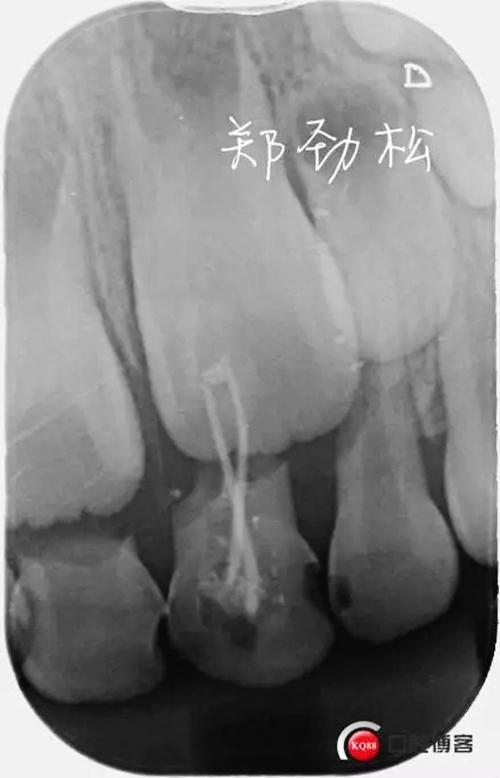

檢查:7A牙體變色,舌側(cè)有充填物,叩診(++),松一度,冷熱刺激無(wú)反應(yīng),唇側(cè)牙齦紅腫有一瘺管。

處置:開(kāi)隨,去除根充物后沖洗引流。

357088.jpg

此病例術(shù)后取出根充物發(fā)現(xiàn)其中有兩根牙膠尖,其實(shí)大家都知道乳牙的牙根隨著恒牙的萌出會(huì)逐漸吸收,而牙膠尖不能被吸收,所以牙膠尖不能夠用作乳牙根充,我常規(guī)選擇vitapex糊劑作為乳牙的根充材料。